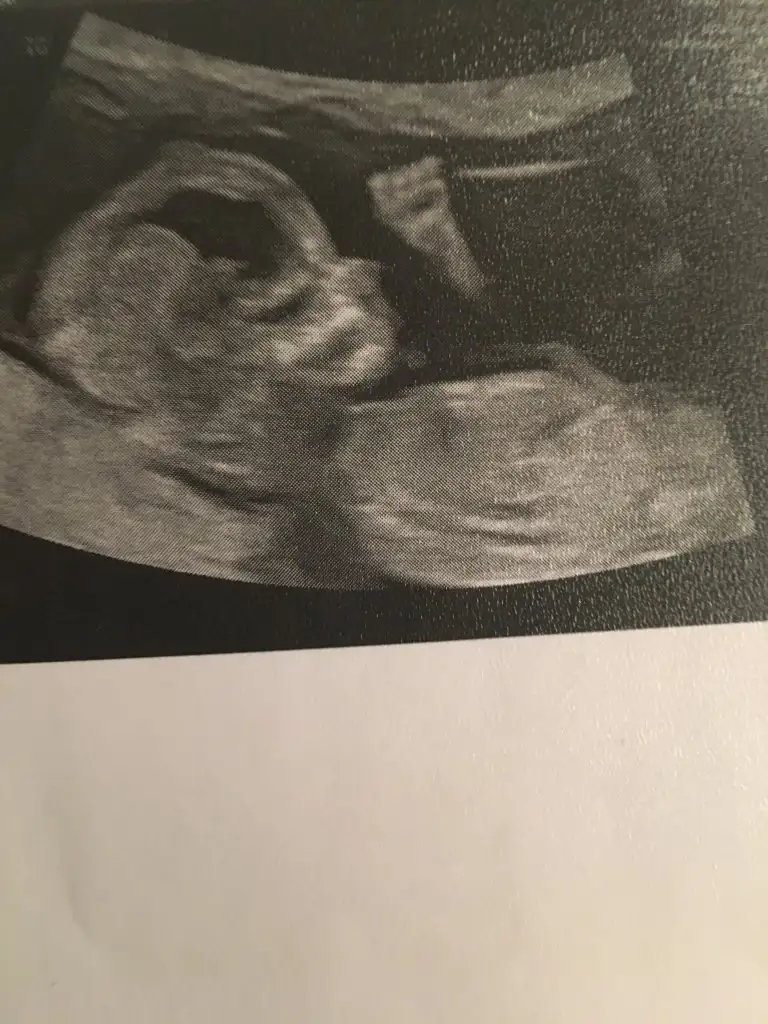

Mutlaka aticam çok teşekkür ederimBuna göre kız ama en iyi 11 12 13 haftalar olmalı

Ben yüzde 60 erkek yüzde 40 kız diyorumIkraammmm bugun girdim ultrasona dr 10+5 gunluk dedi belli oluyormu burda canim Eki Görüntüle 2676525 Eki Görüntüle 2676526 Eki Görüntüle 2676525

Hadi bakalim mely 15 Insallah %60 lik olur Valla ikinci kizimdan sonra cokta heves etmek istemiyorum kizdir diyip kendimi alistirmaya calisiyorum hamd olsun Allaha iki tanr pirlanta gibi nur kizim var bu oglan olsun sonrakiler yine kiz olsun istr gonul istiyor yapacak bisey yok RABBIM zengin isteyin kullarim buyurdu istedik kabul buyurur duamizi Insallah sanada bir kiz nasip eder Insallah canim cok sagol yorumun icin ikrayada sanada cok tesekkur ederimBen yüzde 60 erkek yüzde 40 kız diyorum

İnşallah canım hayırlısı erkek olma ihtimali yüksek bebeğinin sağlıkla gelsin gönül olmayanı istiyo isteHadi bakalim mely 15 Insallah %60 lik olur Valla ikinci kizimdan sonra cokta heves etmek istemiyorum kizdir diyip kendimi alistirmaya calisiyorum hamd olsun Allaha iki tanr pirlanta gibi nur kizim var bu oglan olsun sonrakiler yine kiz olsun istr gonul istiyor yapacak bisey yok RABBIM zengin isteyin kullarim buyurdu istedik kabul buyurur duamizi Insallah sanada bir kiz nasip eder Insallah canim cok sagol yorumun icin ikrayada sanada cok tesekkur ederim